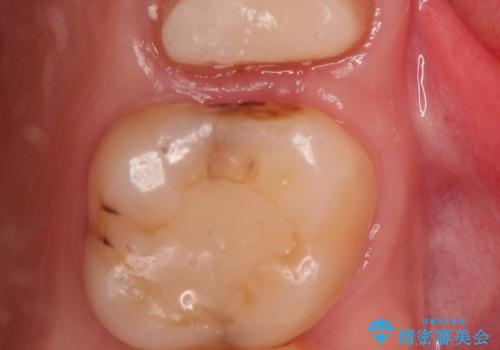

かぶせ物と詰めてある修復物を除去すると歯肉の中まで虫歯になっていました。

歯を部分矯正で引き上げて、虫歯を徹底的に取り除き、適合の良いかぶせ物を装着する計画としました。